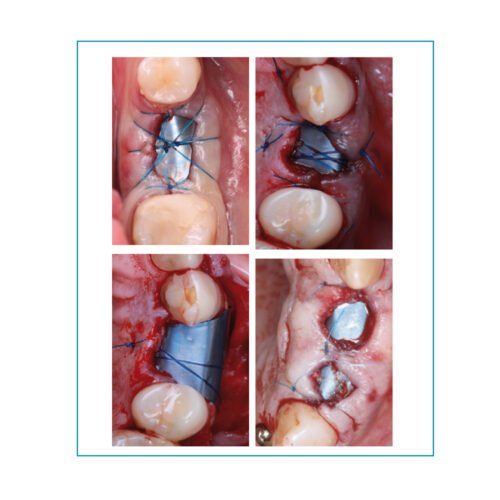

Surgitime PTFE 0,25 mm formato H

Surgitime Titanio 0,15mm

Surgitime Titanio 0,85mm

Surgitime Titanio 0,85mm Bold

Surgitime Titanio Seal